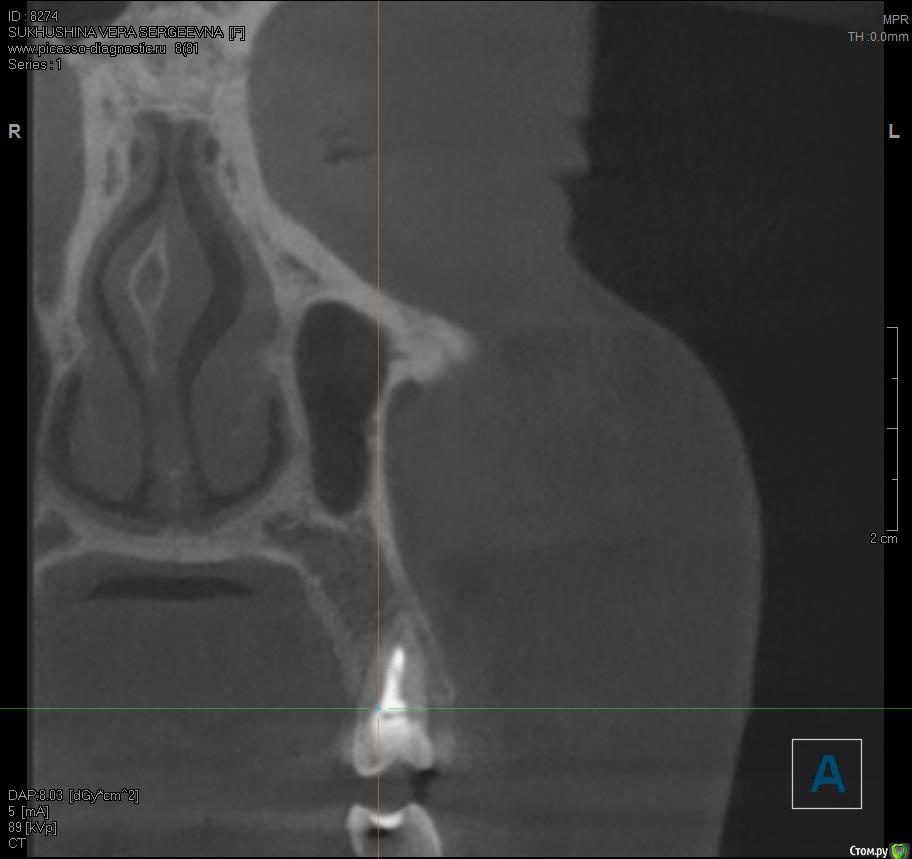

Verasss Опубликовано 28 сентября, 2016 Автор Поделиться Опубликовано 28 сентября, 2016 эх, ну два врача мне зуб делали. один нерв вынимал, второй пломбировал, так уж вышло. и снимки там разных проекций и КТ есть. Дело не в этом. Когда оставила зуб в покое, жизнь постепенно наладилась, но вернулась с дождями-холодами числа 22.09.Уже и бегала к хирургу, показаний для разреза нет, отека нет. По КТ вроде в гайморовой то ли киста то ли полипы. Гноя, насморка нет. Болит и она периодически.Но больше беспокоит, что ноет десна и ощущение мягкости, ноет не в карманах, а в где-то в верхушке корня что ли. Если сильно втянуть воздух, то как бы весь зуб ощущается в этом периодонте и отдает в гайморову. И 6-ка тоже стала немного чувствительной перкусии.На холод-тепло сам зуб не реагирует, сам зуб вообще не беспокоит, только ткани вокруг него.А как болит канал мне показали, дунув хорошенько воздухом в стоматологии на 6-ку рядом (там пломба близко к нерву), и вот это не такая боль. А вообще, день на день не приходится. То гайморова беспокоит, до десна, то всё вместе, то почти ничего. Основные раздражители: механические (например, тряска в маршрутке, трогание зуба языком, чистка зубной нитью, твердая пища), дожди-холода, психологические (тревога, стресс). Причем в один день зуб может не беспокоить, ткани ощущаться твердыми, а в другой разныться. КТ прилагаю архивом от 08.09. К сожалению, чтобы нарезать фотки, мне нужно переустанавливать память с бОльшей мощностью, а такой возможности у меня пока нет. Надеюсь, кто-нибудь посмотрит). https://yadi.sk/d/5Zw3pMFevs7Hd Делать снимки свежие уже боюсь, уже много чего наделано, и на визиографе, и простых рентгенов, и КТ. В общей сложности где-то +10. Ещё и лоры требуют, чтоб я делала КТ пазух с их точки зрения, а государственный - чтоб вообще рентген сделала в поликлинике. В общем, засада. Хочется какой-то универсальный сделать. Может, физио поделать? Т.е. у меня как пациента по-прежнему 2 варианта: или острое воспаление, которое не видит КТ от недопломбировки верхушки или занесения чего-либо, а гноя нет, может, иммунитет хилый, свищ не делает, а если вскрыть зуб, то пойдет? был отек губы и немного щеки как-то после очередных постукиваний у стоматолога, но я выпила антибиотик, и на следующий день прошло. (плюс я антибиотики пропила курсом и анальгин иногда); и вообще воспаления у меня всегда так проходят сразу в хронической форме, долго и мутно, без горячки и адовых болей. (Хотя....если можно как-то сравнить с ногой, например, в прошлом году, то там был гнойник с опуханием всей стопы, всё как в учебнике...) Или это сильная травма зуба и периодонта при пломбировке горячей гутапперчей, усиленная моими походами к стоматологам и постукиванием там по оному. Гайморова присоединилась не сразу, а где-то недели через 2 после пломбировки. Т.е. как-то мне видится, что врачи правы,и там не гайморит, а была уже большая киста или полипы, которую эта агрессивная пломбировка потревожила. Спасибо!Если кто ответит, и на том спасибо). Ссылка на комментарий

Verasss Опубликовано 27 октября, 2016 Автор Поделиться Опубликовано 27 октября, 2016 К сожалению, глаза болят, не могу я нарезать КТ. Сделала КТ пазух по направлению ЛОРов: киста левой гайморовой пазухи, киста левой клиновидной пазухи. Никаких гайморитов, синуситов не было вообще, последняя простуда - несколько лет назад. И сейчас гайморита не было и всеми исключен. Возможны ли все эти кисты от зуба? Жизнь была прекрасна до пломбировки 25 зуба. Теперь 2 кисты слева, лицевые боли, проблемы с глазами, хожу в солнезащитных очках, светобоязнь и боязнь сверкающих предметов, на левом глазу ухудшилось зрение, ноющая боль в периодонте 25 зуба сохраняется, если потревожить, начинает поднывать, развивается и требует обезболивания. Неврологические препараты снимают симптоматику на лице. К вечеру - обострение ухудшений зрения и паника. Вопрос: если мне сделают операции по удалению кист пазух, возможно ли, что они снова возникнут и начинать следует с зуба? Ссылка на комментарий

Verasss Опубликовано 30 октября, 2016 Автор Поделиться Опубликовано 30 октября, 2016 Лицевые боли почти прошли, подотпустило с зубами, и даже глаза как-то почти "встали на место". Температуры нет. Но последнее время слабость, небольшая какая-то неуверенность в равновесии, рассеянность, сонливость. По городу - на такси. Мне бежать к врачам надо или ничего? Может, от финлепсина? Сделала КТ пазух по направлению ЛОРов: кистоподобное образование левой гайморовой пазухи, кистоподобное образование левой клиновидной пазухи. Возможны ли все эти кисты от пломбировки зуба? Потому как все образования слева и раньше таких "ощущений" (ни приведи господи никому) у меня не было. В порядке бреда, а может это быть вообще жидкостное образование, которое возникло по типу отека после травмы, как бывает при переломе ноги и т.д? И как бы натекло ещё и в клиновидную за глаза? И ещё в порядке бреда, а может это из клиновидной перейти в череп и мозг, и от этого сонливость, рассеянность, проблемы с равновесием и т.д? И если оперировать эти кисты, то не может ли снова нарасти что-то, если, скажем, на корне всё равно инфекция? Или можно оперировать только, когда всё спокойно в периодонте? Ссылка на комментарий

Verasss Опубликовано 23 ноября, 2016 Автор Поделиться Опубликовано 23 ноября, 2016 Сделала ещё 1 кт, спустя почти 2,5 месяца после первого. Посмотрите, пожалуйста, есть ли изменения? Напомню, что пункцию гайморовой мне сделали. Ссылка на комментарий